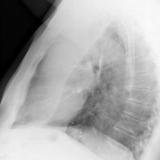

LUL Collapse Case 1 Lateral

Date: 02/19/2004

Views: 3839